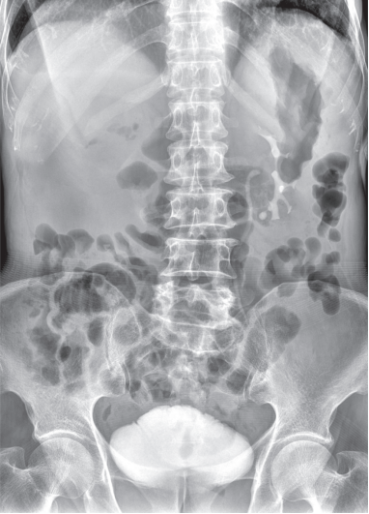

该系统核心优势在于整合动态透视与三维成像技术。在脊柱全长摄影、双下肢负重位检查中,可一次性获取颈椎至骶尾椎的高清全景影像,避免传统分段拍摄的拼接误差,为脊柱侧弯、关节畸形等疾病的力线测量和手术规划提供精准数据。其动态功能成像模块能实时捕捉关节运动状态下的解剖结构变化,清晰显示膝关节屈伸、肩关节活动时的软组织动态,显著提高韧带损伤、关节不稳等隐匿性病变的检出率。